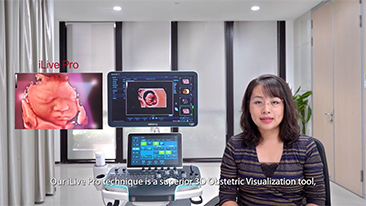

Unsere L?sungen zur Bildgebung orientieren sich am Bedarf der ?rzte und des Pflegepersonals, sowie am Wohl der Patienten. Wir verfolgen damit das Ziel, genauere Diagnosen und eine zuverl?ssige Behandlung in verschiedensten medizinischen Bereichen zu erm?glichen.

Optimierte OBG-Workflows sind n?tig, wenn gro?e Patientinnenzahlen im Rahmen von Gesundheitsscreenings bew?ltigt werden sollen. Zum Beispiel sind Fehlbildungen des zentralen Nervensystems (ZNS) eine der h?ufigsten angeborenen Anomalien. Wegen verschiedener f├╝r die Bildgebung ung├╝nstiger Bedingungen, etwa eine schwierige Position des F?tus, ist es besonders schwer, die MSP von 2D-Ultraschall zu erhalten. Aus diesem Grund k?nnen automatisierte Erkennung und Messungen die Scanning-Effizienz deutlich steigern.